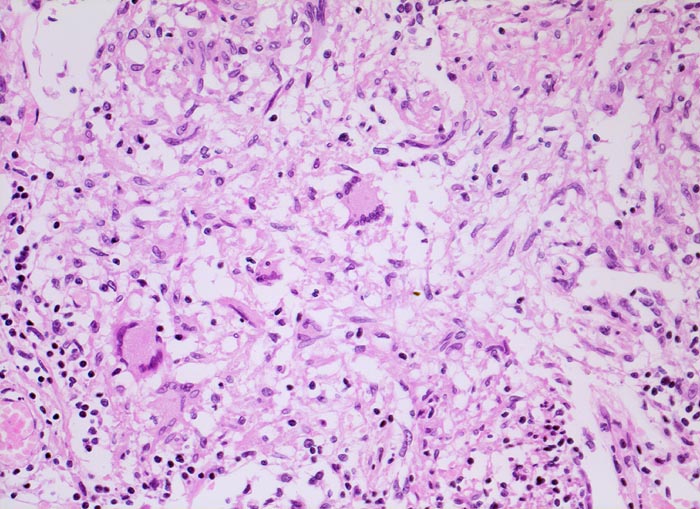

Das morphologische Bild ist äusserst variabel. Je nach Abwehrlage, Art und Geschwindigkeit der Ausbreitung entstehen unterschiedlich grosse, teils geschichtete Herde mit unterschiedlichem Grad an Epitheloidzellreaktion, zentraler Nekrose bzw. Vernarbung. Rein produktive Granulome ohne Nekrosen sind Zeichen guter Abwehrlage. Der Begriff Verkäsung bezieht sich auf den makroskopischen Aspekt von Nekrosen, der an Frischkäse erinnert. Exsudative nekrotisierende Granulome entstehen bevorzugt bei schlechter Abwehrlage. In späteren Stadien der Lungentuberkulose unterscheidet man produktive Phthisen mit azinös nodösen Gruppen von bronchogen entstandenen gering verkäsenden Streuherden (Präparat), zirrhotische Phthisen mit gering verkäsenden stark vernarbenden Herden und exsudative Phthisen bei schlechter Abwehrlage. Bei letzterer steht die Verkäsung im Vordergrund. Die bakterienreichen Herde entstehen teils hämatogen, teils bronchogen. Verkäsende Herde sind Ausgangspunkt für die Kavernenbildung. Kavernen stellen die wichtigste Quelle für die bronchogene Streuung dar.

• Granulome mit zentraler käsiger Nekrose mit Kerntrümmern umgeben von einem Epitheloidzellwall und einem äusseren blauen Saum von Lymphozyten.

• Schlanke spindelige Epitheloidzellen und einzelne Riesenzellen vom Langhanstyp mit peripher hufeisenförmig angeordneten Kernen.